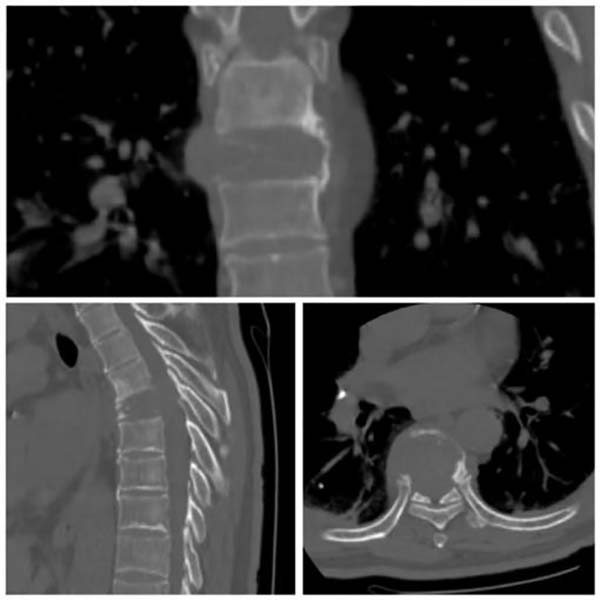

图1 胸椎CT和MRI提示胸椎7椎体骨破坏,椎旁肿胀,相应水平椎管狭窄,脊髓明显受压。

该患者经胸椎穿刺活检,确诊为肾癌胸椎转移。考虑到一期手术切除肿瘤会导致大量出血,而且单纯后路手术难以完整切除肿瘤,经全科讨论后最终制定了这一联合治疗方案。手术过程中,医生在C臂引导下将氩氦刀精准插入胸椎椎体病灶,通过快速冷冻和复温,成功地将肿瘤组织彻底摧毁,同时最大限度地保护了周围正常组织。联合后路椎管减压术和脊柱内固定术,有效解除了脊髓压迫, 并重建了脊柱稳定性,患者的疼痛和不全瘫症状得到明显改善。此次治疗也为二期行前路肿瘤切除、骨水泥或钛网重建前柱奠定了良好基础。